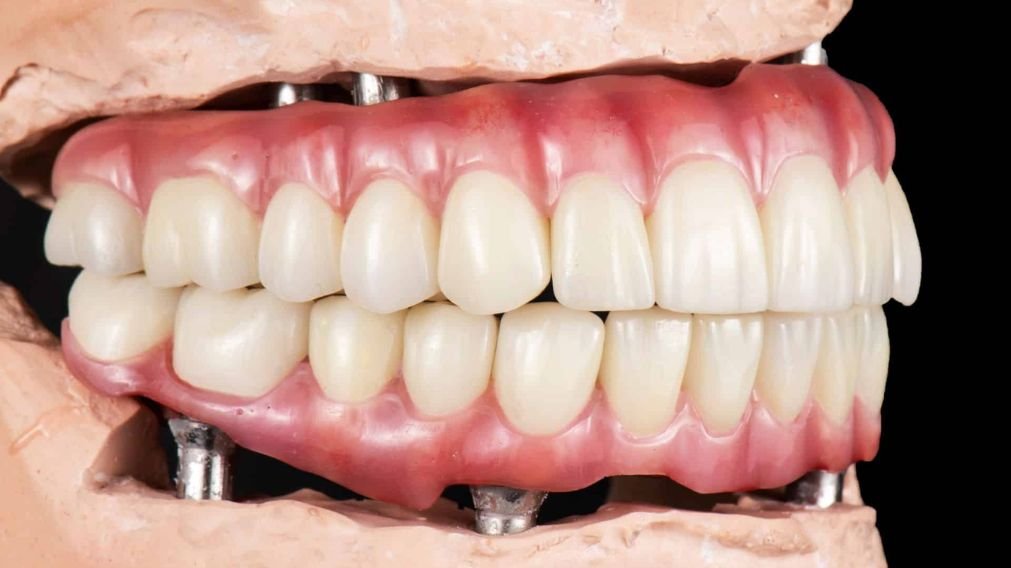

A prótese protocolo, também conhecida como “dentadura fixa” ou “ponte fixa sobre implantes”, é uma solução de reabilitação oral completa para pacientes que perderam todos os dentes de uma arcada (superior ou inferior). Trata-se de uma estrutura única contendo todos os dentes (geralmente 12), que é parafusada de forma permanente sobre um número estratégico de implantes de titânio (geralmente 4 ou 6).

- Protocolo All-on-4: Utiliza 4 implantes. É a solução ideal para a maioria dos casos, especialmente quando há alguma perda óssea na região posterior, pois utiliza implantes angulados para evitar a necessidade de enxertos. Saiba mais sobre o All-on-4 aqui.

- Protocolo All-on-6: Utiliza 6 implantes. É indicado para pacientes que precisam de estabilidade máxima, como aqueles com osso de baixa qualidade (comum na maxila) ou bruxismo severo. Os dois implantes adicionais distribuem melhor as forças mastigatórias. Saiba mais sobre o All-on-6 aqui.